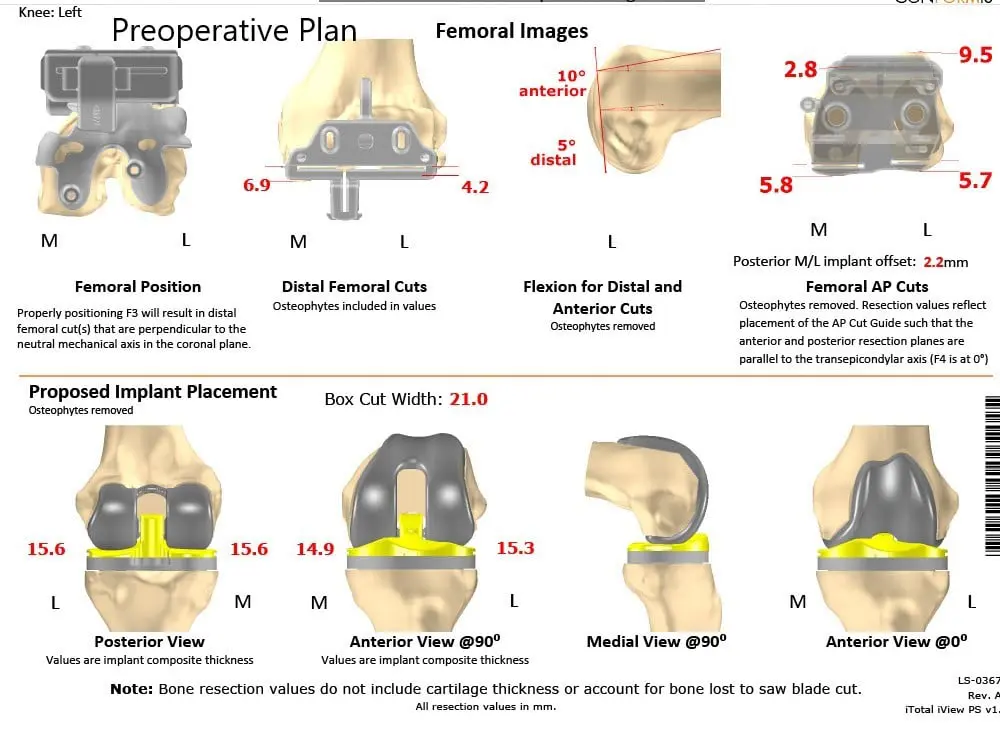

The patient underwent a CT scan 3 weeks prior to the procedure. A preoperative plan was formulated based on the patient’s anatomy and biomechanics. The plan outlined the bone cuts for maximum bone preservation and accurate duplication of natural knee biomechanics. The CT scan images were used to construct custom implants and instruments uniquely designed for the patient.

Complete Orthopedics patient-specific surgical plan for customized total knee replacement in a 59-year-old male (scan 2)